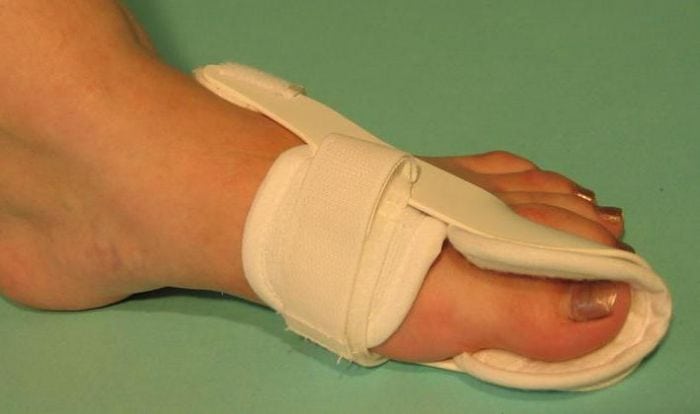

Основные методы лечения

С самого начала лечения пациентам показано ношение специальных ортопедических приспособлений для обеспечения правильного анатомического положения стопы. Используются межпальцевые вкладыши, супинаторы, накладки различной жесткости, предупреждающие дальнейшую деформацию плюснефалангового сустава. Ортопедические приспособления также помогают избежать развития воспалительного процесса из-за натирания мягких тканей.